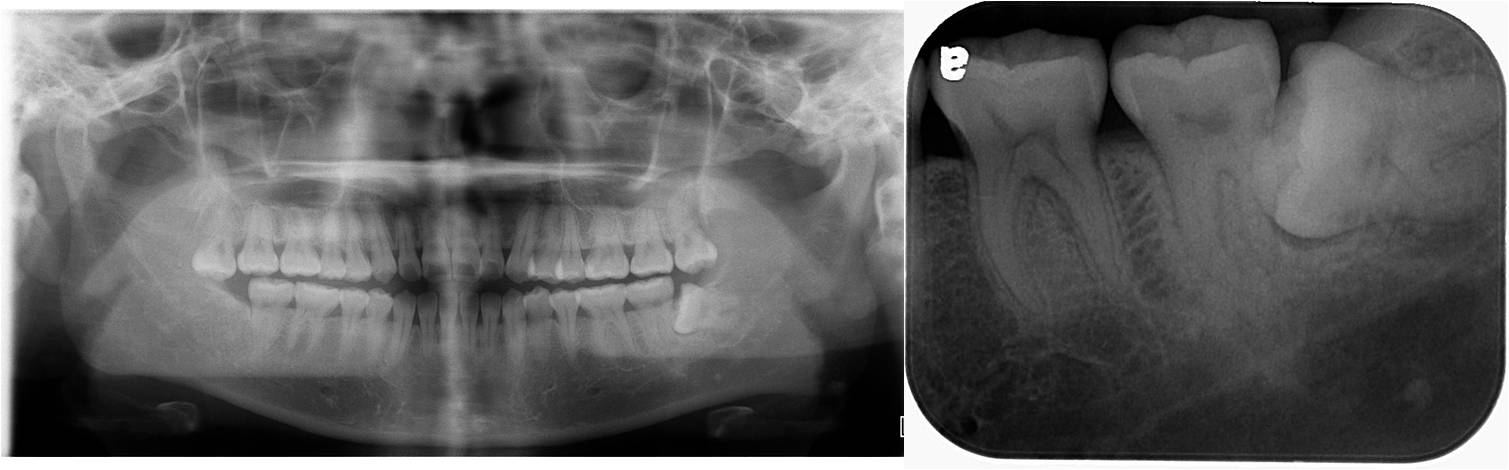

左下阻生齒:術前X光-水平智齒